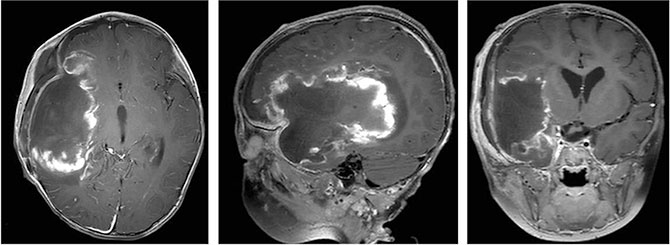

肿瘤被完整切除,切除组织大小约13×7×4厘米

周东主任凭借多年的临床经验和高超的手术技艺,精准掌握手术节奏,确保了每一步操作的成功。在团队的通力合作下,肿瘤最终被完整切除,切除组织大小约13×7×4厘米。术后患儿恢复良好,意识状态逐渐改善,可自主进食,右侧肢体肌力逐步恢复,术后一周已能在搀扶下站立,未出现新发神经功能障碍。复查头部MR显示肿瘤全切,周围脑组织受压解除,脑中线结构复位。

术后影像资料显示肿瘤全切